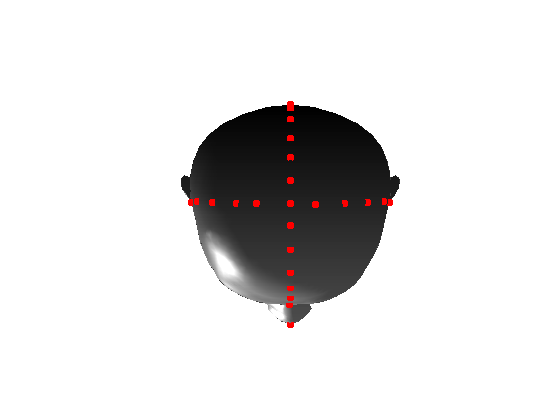

Pose is normalised using the ECN method, and relies on the symmetry plane, ellipse centre and nasion position, as shown in Fig. 25. We then find a set of pseudo-landmarks on the cranial surface by 3D ray projection over a predefined set of angles, as shown in Fig. 26. The same processes are applied to a template mesh of the human head, so that it has the same set of both face and cranium landmarks.

|

|

|